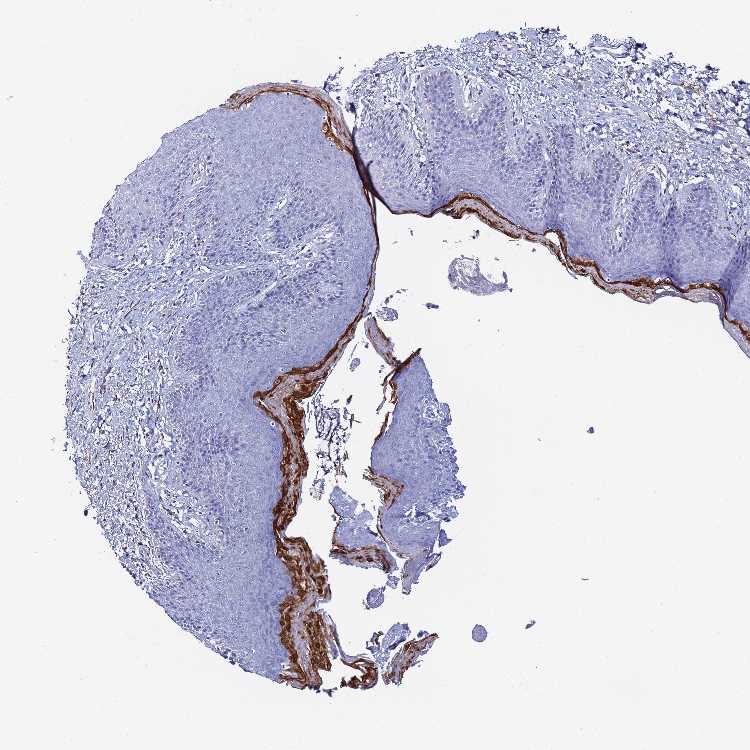

SKIN 1 - Antibody stainingi

Antibody staining in the annotated cell types in the current human tissue is reported as not detected, low, medium, or high, based on conventional immunohistochemistry profiling in selected tissues. This score is based on the combination of the staining intensity and fraction of stained cells.

Each image is clickable and will lead to virtual microscopy that enables deeper exploration of all samples and also displays staining intensity scores, fraction scores and subcellular localization as well as patient and tissue information for each sample.

Antibody HPA042216

Langerhans Not detected

Fibroblasts Not detected

Keratinocytes Not detected

Melanocytes Not detected